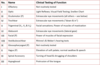

List the key areas for testing the sensory afferent of the Trigmeninal Nerve

- Ophthalmic (CNV1):

- forehead, upper eyelid & tip of nose

- Maxillary (CNV2):

- mid-cheek, lower eyelid, upper lip & nostril of nose

- Mandibular (CNV3):

How would you clinically test the Sensory afferent of the trigemnial nerve?

- Ask the patient to close their eyes

- Gently brush the skin in each dermatome with a fine tip of cotton wool

- Ask the patient to tell you when they feel their skin being touched

- Compare the 2 sides

How would you clinically test the motor efferent of the trigeminal nerve?

- Palpate the strength of contraction of the masseter & temporalis by asking patient to clench their teeth

- Ask the patient to open their jaw against resistance